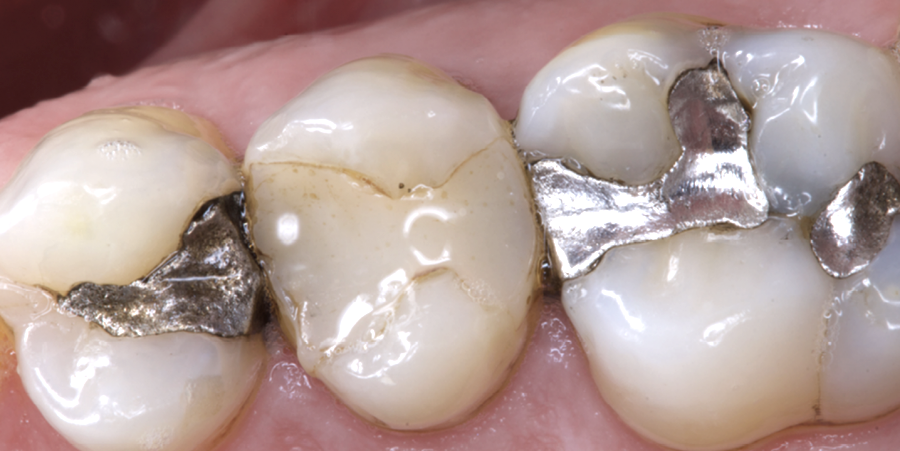

Le Parlement européen a adopté le 17 janvier, en première lecture, la proposition de règlement de la Commission européenne visant à supprimer totalement l’utilisation, la fabrication et l’exportation des amalgames dentaires dans l’ensemble des pays de l’Union à compter du 1er janvier 2025.

Depuis le 1er janvier 2018, l’utilisation des amalgames est interdite dans l’Union sur des dents de lait, pour les mineurs de moins de 15 ans et les femmes enceintes ou allaitantes.